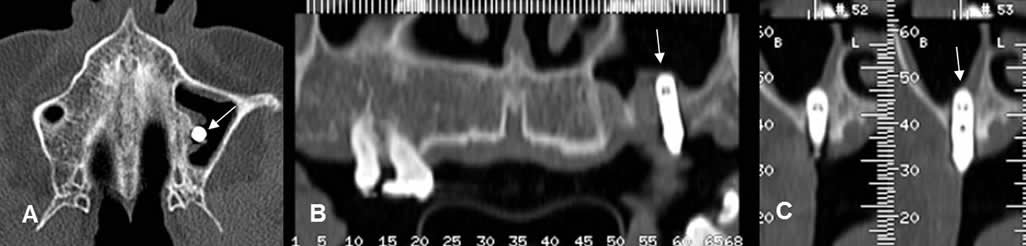

Fig 20 A. Raíz retenida.

A: TAC axial, B: TAC reconstrucción panorámica y C: TAC sagital.

Ausencia de piezas, en el lado izquierdo del maxilar, con fragmento de raíz retenida.